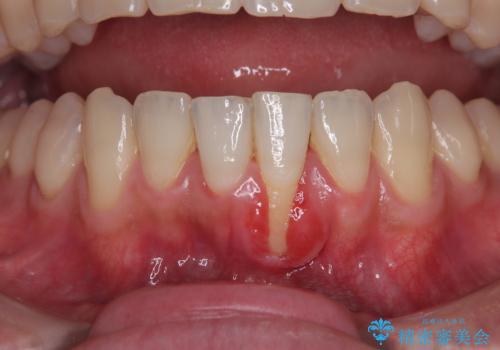

欠損部の歯肉が窪んでいるため、歯肉移植により形態を改善し、オールセラミックブリッジにて補綴することとしました。

事前に装着されていた接着タイプのブリッジは、歯の切削量が少ない反面、接着界面から虫歯が進行しやすく、脱落リスクが高くなるというデメリットがあります。

- 外科手術のため、術後に痛みや腫れ、違和感を伴います